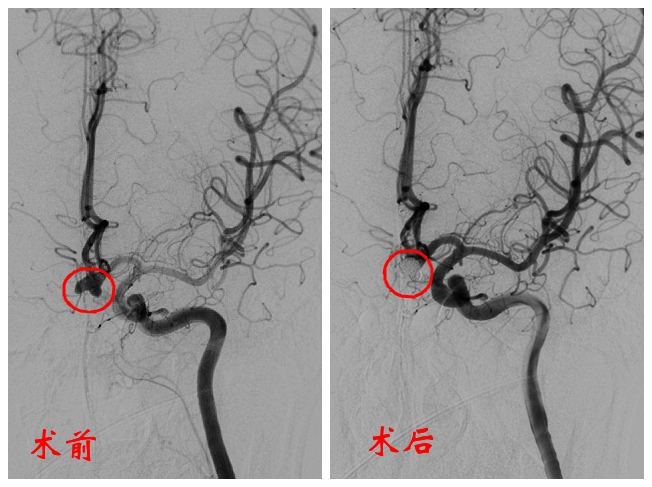

神经外科介入团队紧急开展DSA血管造影术和经导管颅内动脉瘤介入栓塞术。

介入栓塞治疗就是通过细小导管将弹簧圈填塞进动脉瘤瘤体,防止血液流入瘤体,避免动脉瘤再次破裂出血。

术中发现,动脉瘤直径约8-9毫米,有三个凸起,类似枫叶。动脉瘤不规则的形状增加了填塞的难度,手术团队历时两个多小时,填塞了十多个弹簧圈才顺利完成手术。

术后CT显示患者颅内未见再发出血,原出血部位吸收良好。